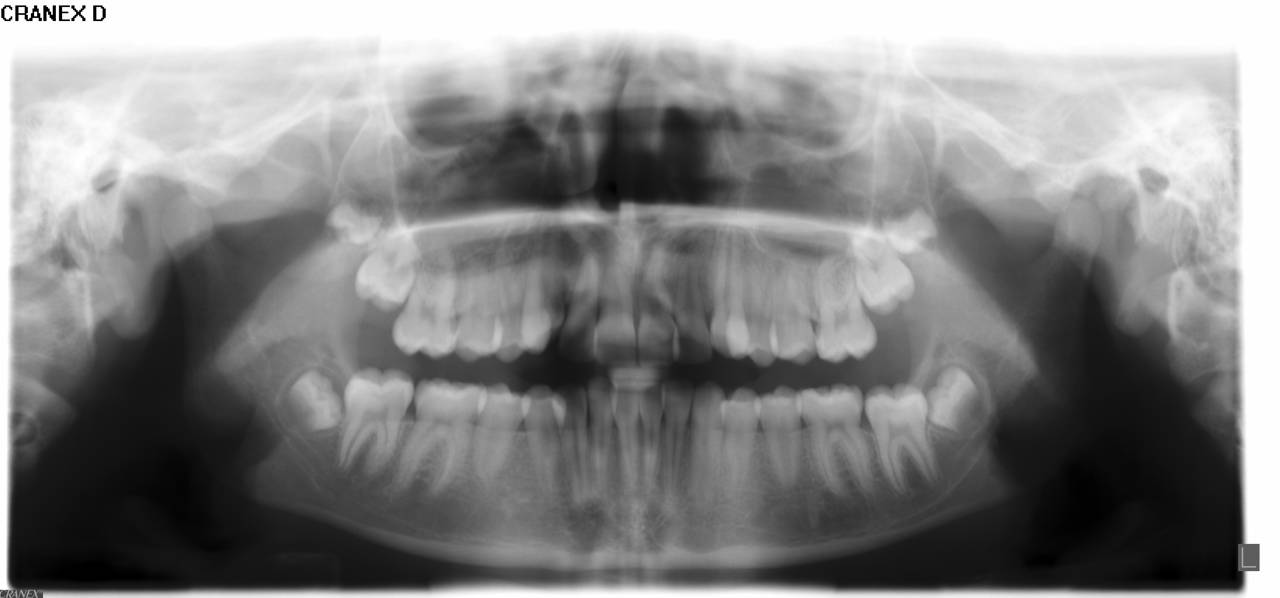

- Panorama viser, om alle tænder er anlagt, og om tandrødder og kæbeled ser normale ud.

- Profilrøntgen giver et billede af, hvordan kæberne er placeret i forhold til hinanden og i forhold til resten af kraniet. Derudover giver det et indtryk af, hvordan væksten vil udfolde sig.

- Alt materiale studeres af en specialtandlæge, der udarbejder en behandlingsplan.